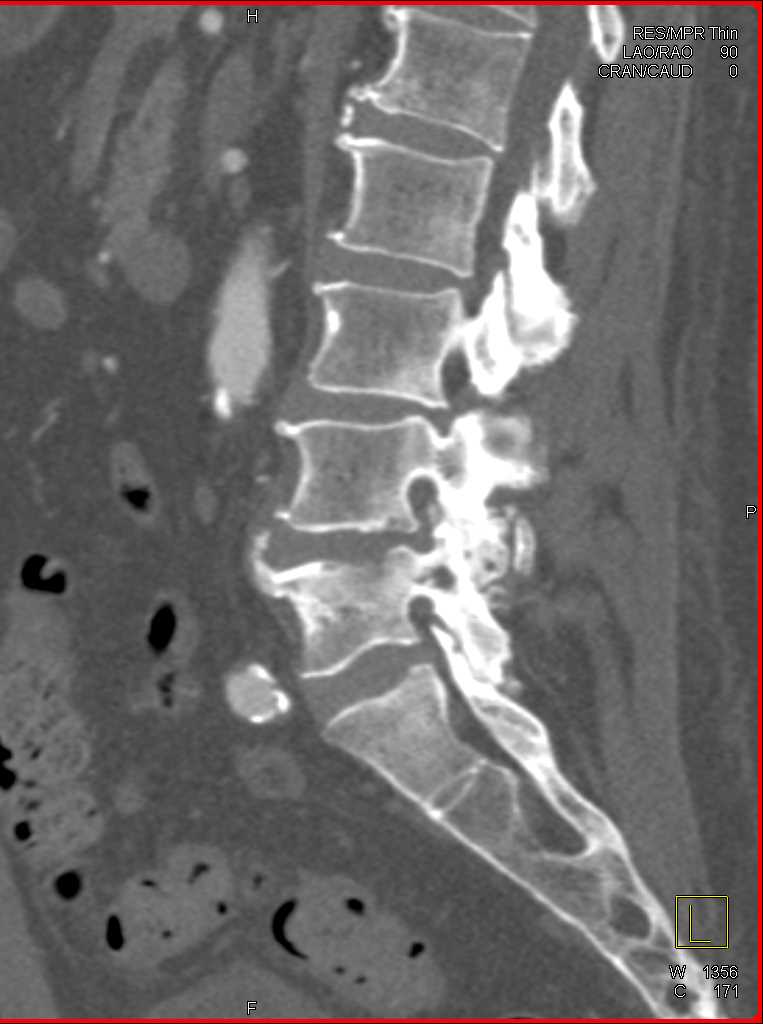

Infection at L4-L5 interspace